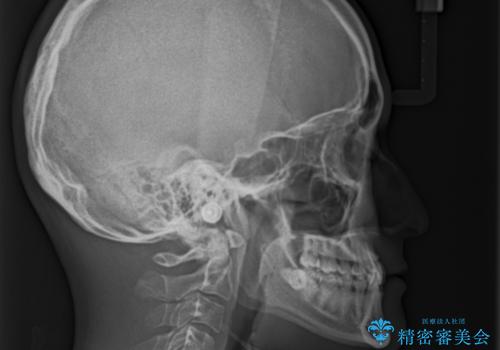

- 上下の前歯のデコボコを改善したいと来院された患者様です。

上顎の歯列幅が狭く、それによって歯が並ぶスペースが不足しています。

また下顎の歯列幅も制限され、内側に歯が倒れています。

それらを改善するため上顎に拡大装置を用いて、審美装置にてワイヤー矯正を行いました。

上顎が側方に拡大されて歯が並ぶスペースを確保できました。

それに伴い下顎の歯列も拡大され、舌側に倒れているのが改善されました。